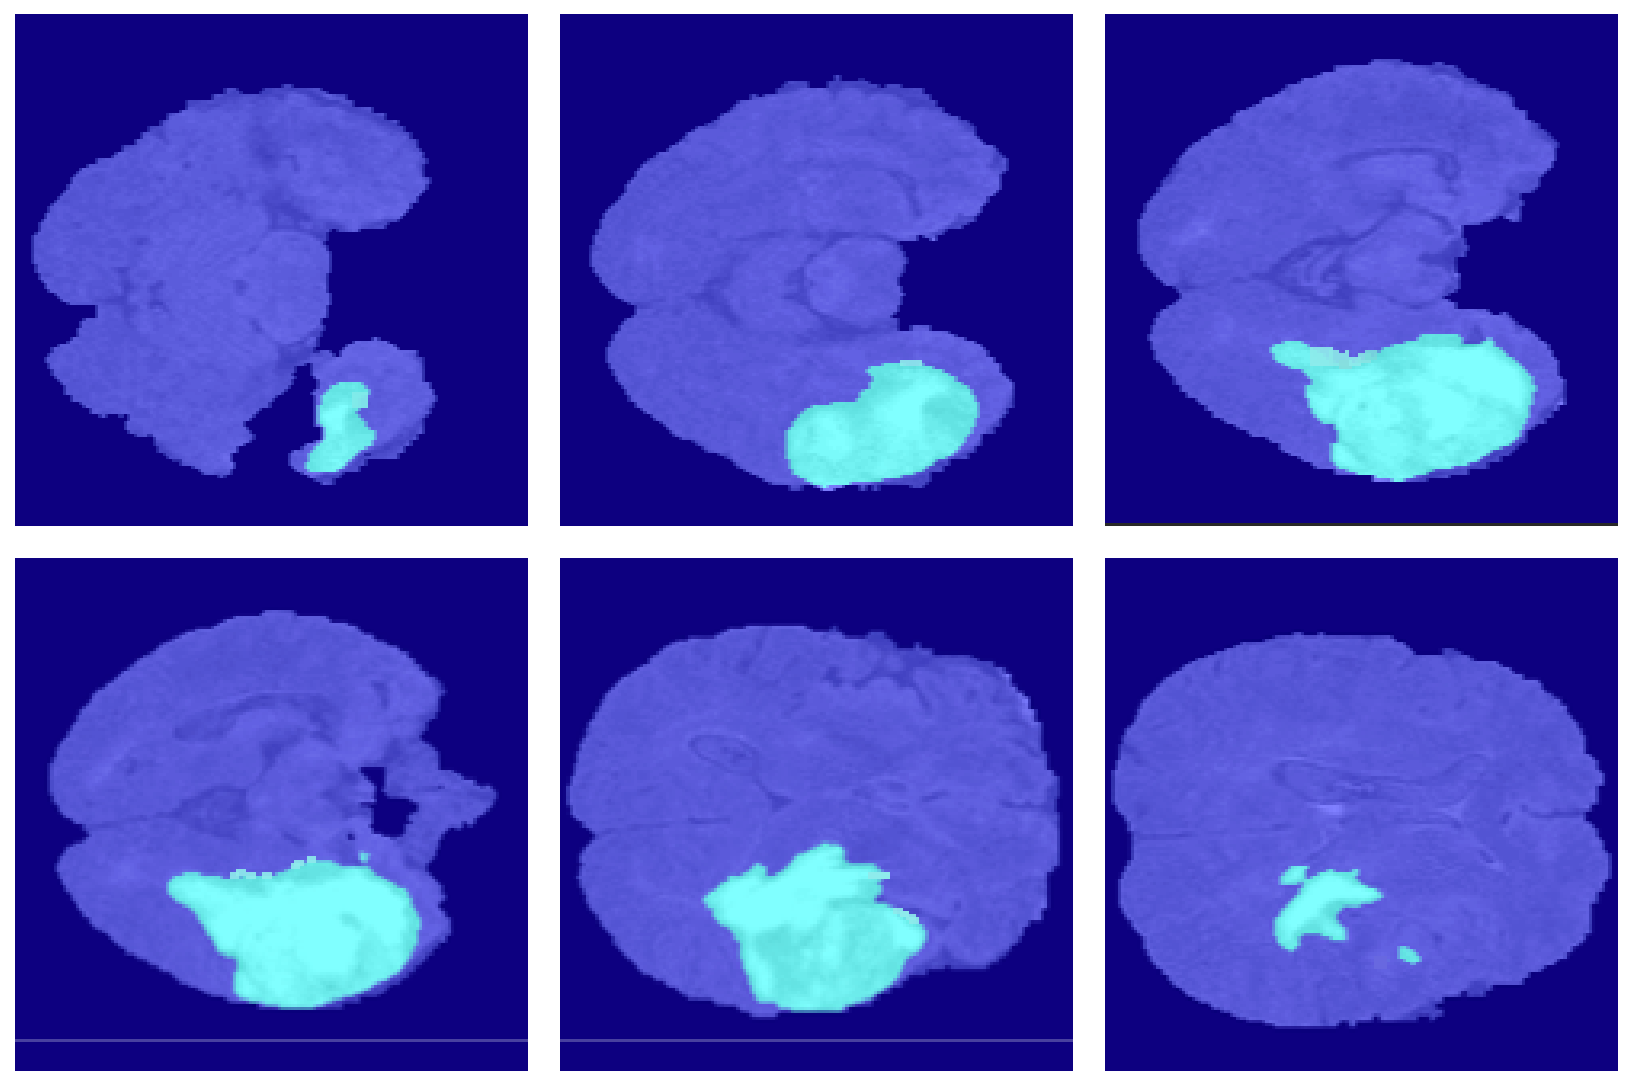

4.2. Segmentation Results

5.6.1. Segmentation Boundary Loss

5.6.2. Third Dimensional Information Loss